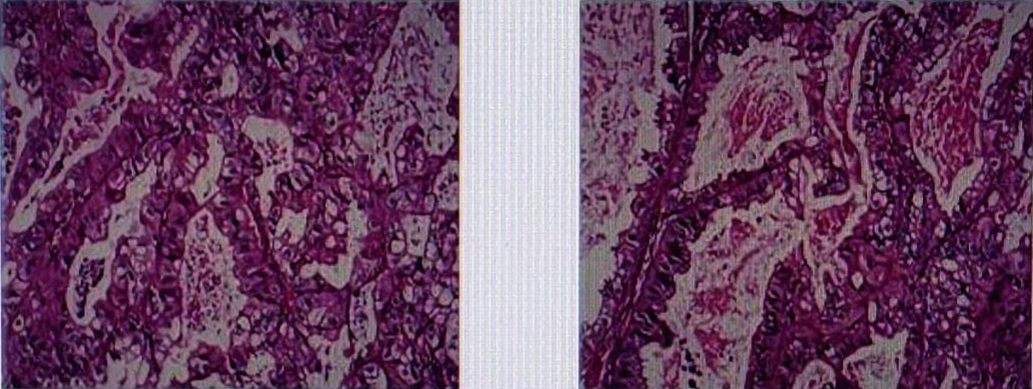

术后病理提示(图3):胃中分化腺癌累及胃壁全层,伴小弯侧淋巴结8/14枚癌转移(可见脉管内癌栓,未见神经侵犯),两断端、大弯侧淋巴结4枚及第4组淋巴结1枚未见癌。

免疫组化结果显示:Her-2(3+),Ki67(20%),CK8/18(+),CDX-2(-),VILLIN(+),CD20(-)

图3. 胃癌术后组织病理切片

② 2021年1月行“胸腔镜右肺中叶切除术+纵膈淋巴结清扫+胸腔粘连松懈术”。

术后病理提示(图4):右肺中叶转移性腺癌,考虑来源于胃。支气管旁淋巴结1枚未见癌转移;送检第2、4组淋巴结4枚,第7组淋巴结9枚,9组淋巴结2枚,10组淋巴结4枚,11组2枚均未见癌。

免疫组化结果显示:CK(+),Ki67(10%),CK8/18(+),TIF-1(-),NAPSIN A(+),CK7(+),CK5/6-,P40-,SYN-,CGA-,CD56-,CDX-2-,CK20-。(患者因自身原因术后未行HER2检测)于2021年3月补充免疫组化:Her-2(3+)。

图4. 胸腔镜右肺术后组织病理切片